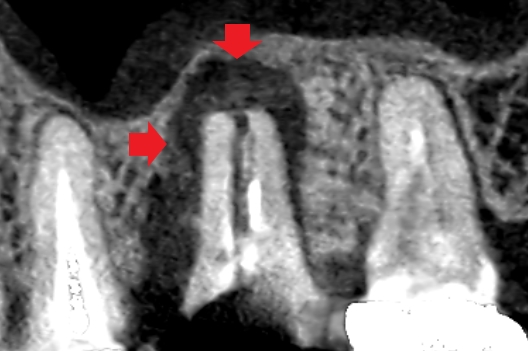

精密再根管治療6ヶ月後の口蓋根の冠状断のCT画像です。舌側の歯槽骨を破って歯肉に到達していた膿の影が消失し、歯槽骨が再生しています(青い矢印)。